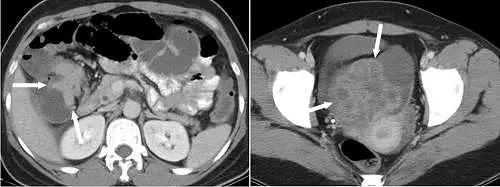

左圖為腹部橫截面 CT,肝彎處可見一不規則腸壁增厚團塊(箭頭),近端迴腸及結腸明顯擴張,符合腸阻塞影像學表現,暗示原發結腸癌。

右圖為骨盆橫截面 CT,可見雙側卵巢區域各有大塊腫瘤,腫塊邊界清晰,內含多重低密度囊性區及實質性軟組織,囊壁強化明顯(箭頭所指),呈現典型混合囊性-實質性外觀,且雙側對稱(右側腫瘤較大、左側亦見小團塊),符合卵巢轉移瘤的特徵。